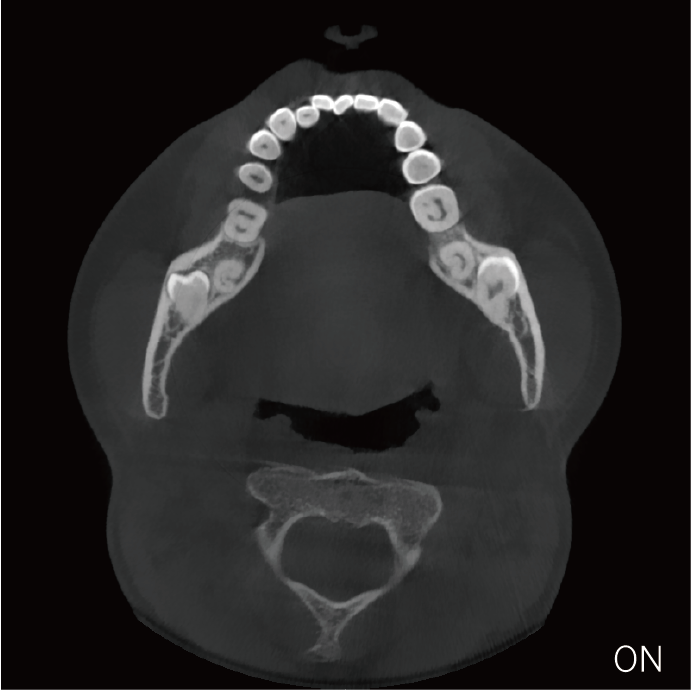

支持局部超清三维显示

局部超清显示、 移动视野摄片

可根据临床需求任意调整成像区域大小实现局部超清三维显示

临床样片